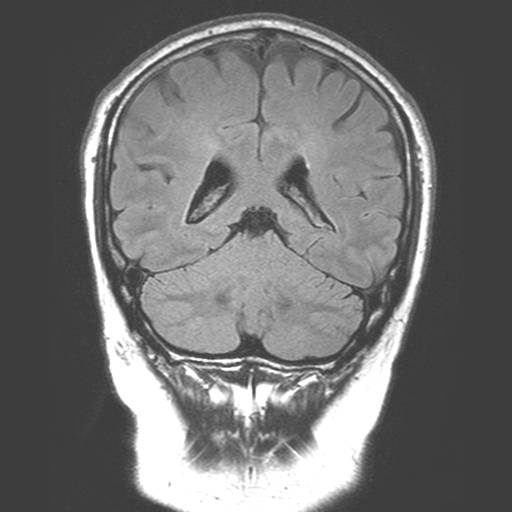

Billede 1: Normal hjerne, tværsnit (set oppefra).

MR-billederne viser fire forskellige optagelser af en normal hjerne. Cerebrospinalvæsken er hvid på billede 1 og 3, mens den er sort på 2 og 4. Man ser tydeligt forskellen på grå og hvid substans i hjernen, det ses bedst på 2 og 4.